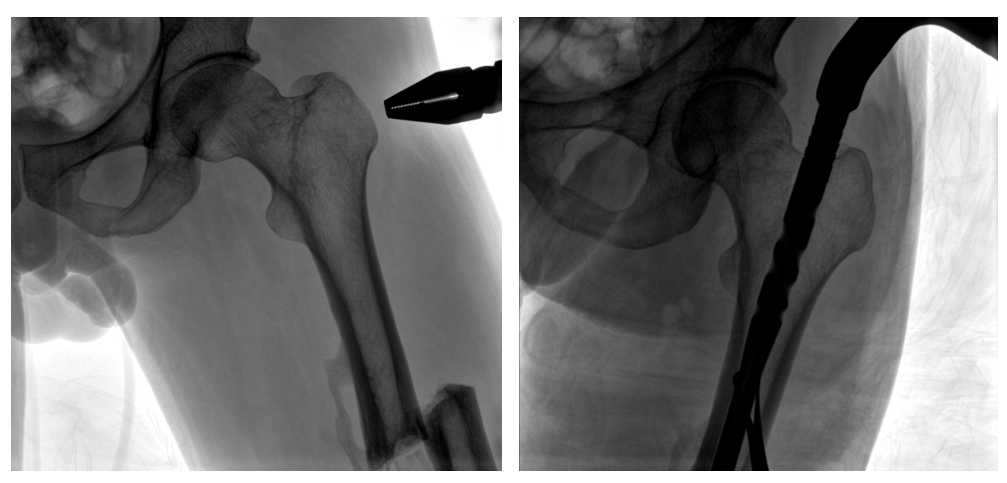

病例二:

患者左股骨干完全骨折,經(jīng)過醫(yī)生評(píng)估,使用“髓內(nèi)釘內(nèi)固定術(shù)”進(jìn)行治療。髓內(nèi)釘內(nèi)固定術(shù)需要將入釘點(diǎn)至骨折部位的影像完全展示,在一些長(zhǎng)骨的骨折中,對(duì)視野范圍要求高。

一體式C形臂釘點(diǎn)至骨折部位的臨床影像

在進(jìn)行髓內(nèi)釘內(nèi)固定術(shù)時(shí),醫(yī)生需要同時(shí)觀察到入釘點(diǎn)和骨折部位的情況,PLX119C大平板一體式C形臂能夠呈現(xiàn)更廣闊的成像面積,滿足大部分長(zhǎng)骨髓內(nèi)釘內(nèi)固定術(shù)的攝片需求。